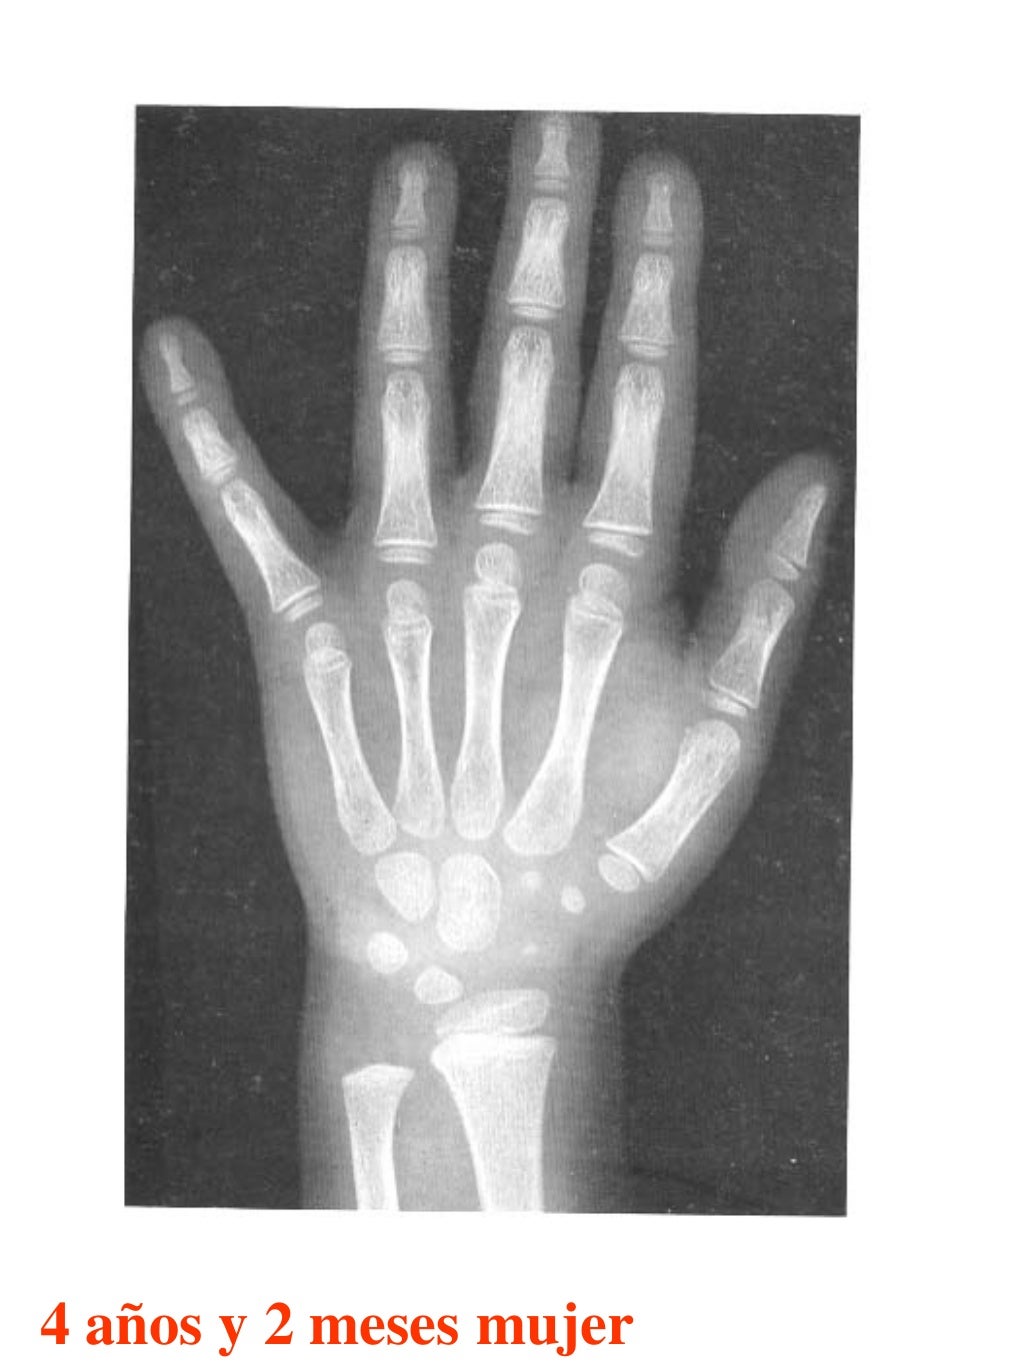

Tablas De Greulich Y Pyle The standards established by greulich and pyle, undoubtedly the most popular method, consist of two series of standard plates. The standards established by greulich and pyle, undoubtedly the most popular method, consist of two series of standard plates. El documento lista las edades. This systematic review summarizes the. The greulich and pyle method is one of the two main ways to assess the bone age of children. Both main methods of bone age. Scribd is the world's largest social reading and publishing site. 153 recomendaciones • 616,869 vistas. Atlas greulich y pyle | pdf | descarga gratuita. The greulich and pyle atlas is used to estimate the age of children and adolescents. The radiographic atlas of skeletal development of the hand and wrist by ww greulich and si pyle is a classic radiological.

Atlas greulich y pyle Tablas De Greulich Y Pyle The standards established by greulich and pyle, undoubtedly the most popular method, consist of two series of standard plates. Atlas greulich y pyle | pdf | descarga gratuita. Scribd is the world's largest social reading and publishing site. 153 recomendaciones • 616,869 vistas. The radiographic atlas of skeletal development of the hand and wrist by ww greulich and si pyle. Tablas De Greulich Y Pyle.

Atlas greulich y pyle Tablas De Greulich Y Pyle Both main methods of bone age. 153 recomendaciones • 616,869 vistas. The greulich and pyle method is one of the two main ways to assess the bone age of children. The standards established by greulich and pyle, undoubtedly the most popular method, consist of two series of standard plates. Scribd is the world's largest social reading and publishing site. This. Tablas De Greulich Y Pyle.